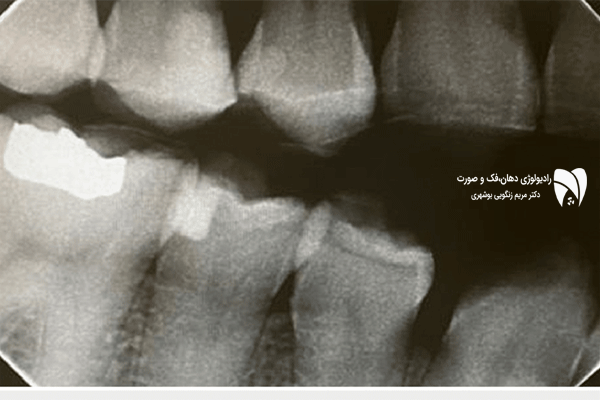

تحلیل حرکت فک یکی از جنبههای کلیدی در بررسی مشکلات فکی و دندانی است. با استفاده از تصویربرداری سهبعدی فک، دندانپزشکان و متخصصان ارتودنسی میتوانند حرکتهای دقیق فک را در شرایط مختلف مشاهده و بررسی کنند. این روش بهویژه در درمان ناهنجاری فک کاربرد دارد و دقت بالایی را در تشخیص مشکلات فکی فراهم میکند. تصویربرداری سهبعدی فک اطلاعات جامعی درباره موقعیت فک، میزان حرکت آن و نحوه تطابق آن با دندانها ارائه میدهد. تحلیل حرکت فک از طریق این روش باعث میشود که درمان ناهنجاری فک با دقت بیشتری انجام شود. استفاده از این فناوری در تحلیل حرکت فک به پزشکان کمک میکند که قبل از شروع درمان، یک برنامه درمانی دقیق را طراحی کنند. در نتیجه، تصویربرداری سهبعدی فک موجب کاهش خطاهای تشخیصی و بهبود کیفیت درمان ناهنجاری فک میشود.

تحلیل حرکت فک از طریق تصویربرداری سهبعدی فک یکی از روشهای نوین در پزشکی است که دقت تشخیص و درمان ناهنجاری فک را افزایش میدهد. این روش امکان مشاهده تغییرات جزئی در حرکت فک را فراهم کرده و اطلاعات دقیقی در مورد ساختار فکی ارائه میدهد. تصویربرداری سهبعدی فک به پزشکان اجازه میدهد که فرآیند درمان ناهنجاری فک را بهینهسازی کنند و نتایج بهتری را برای بیماران به ارمغان بیاورند. تحلیل حرکت فک از طریق این فناوری، امکان شناسایی مشکلات فکی در مراحل اولیه را فراهم میکند که این امر باعث جلوگیری از پیشرفت ناهنجاری فک میشود. همچنین تصویربرداری سهبعدی فک با کاهش نیاز به روشهای تهاجمی، باعث بهبود تجربه درمانی بیمار خواهد شد.

تحلیل حرکت فک با استفاده از تصویربرداری سهبعدی فک دارای مزایای متعددی است که بهبود دقت در درمان ناهنجاری فک یکی از مهمترین آنها محسوب میشود. تصویربرداری سهبعدی فک امکان مشاهده دقیق حرکات فکی را فراهم کرده و پزشکان را در طراحی روشهای درمانی بهتر یاری میکند. تحلیل حرکت فک با استفاده از این تکنولوژی، میزان جابجایی فک را در طول زمان مشخص میکند و به دندانپزشکان کمک میکند تا درمان ناهنجاری فک را با دقت بیشتری انجام دهند. تصویربرداری سهبعدی فک نهتنها به بهبود تشخیص کمک میکند، بلکه امکان اصلاح موقعیت فکی را با روشهای غیرتهاجمی نیز افزایش میدهد.

تحلیل حرکت فک یکی از جنبههای کلیدی در تشخیص مشکلات فکی است که با استفاده از تصویربرداری سهبعدی فک دقت بیشتری پیدا کرده است. تصویربرداری سهبعدی فک این امکان را فراهم میکند که درمان ناهنجاری فک به روش دقیقتر و مؤثرتری انجام شود. این روش، اطلاعات دقیقی درباره نحوه عملکرد فک در طول زمان ارائه داده و امکان بررسی تغییرات کوچک در تحلیل حرکت فک را فراهم میکند. تصویربرداری سهبعدی فک همچنین با کاهش نیاز به تصویربرداریهای متعدد، میزان تابش اشعه به بیمار را کاهش میدهد که این امر موجب افزایش ایمنی بیمار میشود. استفاده از این فناوری در درمان ناهنجاری فک به پزشکان کمک میکند که درمانی مؤثرتر و با نتایج بلندمدتتری را ارائه دهند.